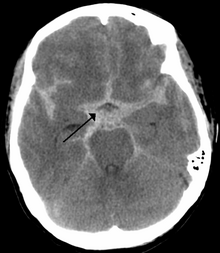

If an aneurysm ruptures, blood leaks into the space around the brain. This is called a subarachnoid hemorrhage. Onset is usually sudden without prodrome, classically presenting as a "thunderclap headache" worse than previous headaches.[6][7] Symptoms of a subarachnoid hemorrhage differ depending on the site and size of the aneurysm.[7] Symptoms of a ruptured aneurysm can include:

Almost all aneurysms rupture at their apex. This leads to hemorrhage in the subarachnoid space and sometimes in brain parenchyma. Minor leakage from aneurysm may precede rupture, causing warning headaches. About 60% of people die immediately after rupture.[8] Larger aneurysms have a greater tendency to rupture, though most ruptured aneurysms are less than 10 mm in diameter.[7]

Rebleeding, hydrocephalus (the excessive accumulation of cerebrospinal fluid), vasospasm (spasm, or narrowing, of the blood vessels), or multiple aneurysms may also occur. The risk of rupture from a cerebral aneurysm varies according to the size of an aneurysm, with the risk rising as the aneurysm size increases.

Once suspected, intracranial aneurysms can be diagnosed radiologically using magnetic resonance or CT angiography.[18] But these methods have limited sensitivity for diagnosis of small aneurysms, and often cannot be used to specifically distinguish them from infundibular dilations without performing a formal angiogram.[18][19] The determination of whether an aneurysm is ruptured is critical to diagnosis. Lumbar puncture (LP) is the gold standard technique for determining aneurysm rupture (subarachnoid hemorrhage). Once an LP is performed, the CSF is evaluated for RBC count, and presence or absence of xanthochromia.[20]